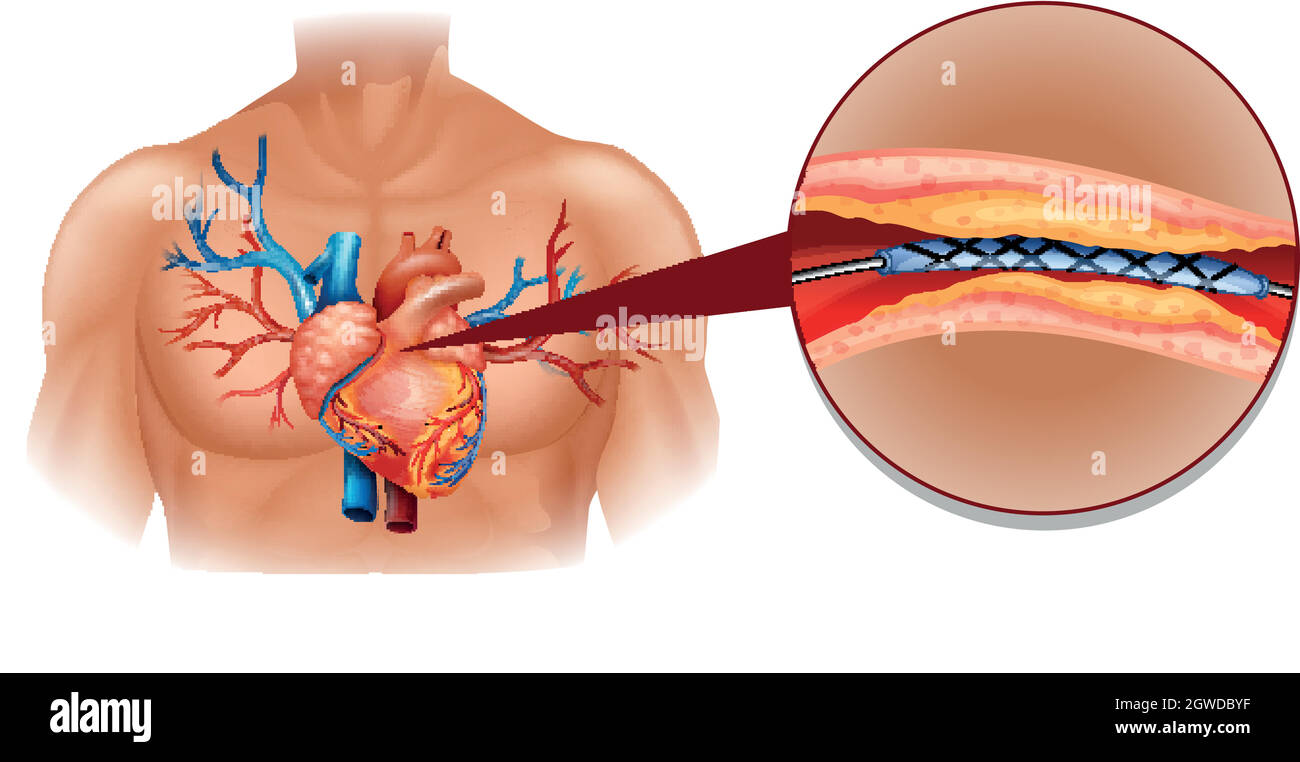

Human heart diagram with balloon tube Stock Vectorhttps://www.alamy.com/image-license-details/?v=1https://www.alamy.com/human-heart-diagram-with-balloon-tube-image445920371.html

Human heart diagram with balloon tube Stock Vectorhttps://www.alamy.com/image-license-details/?v=1https://www.alamy.com/human-heart-diagram-with-balloon-tube-image445920371.htmlRF2GWDBYF–Human heart diagram with balloon tube